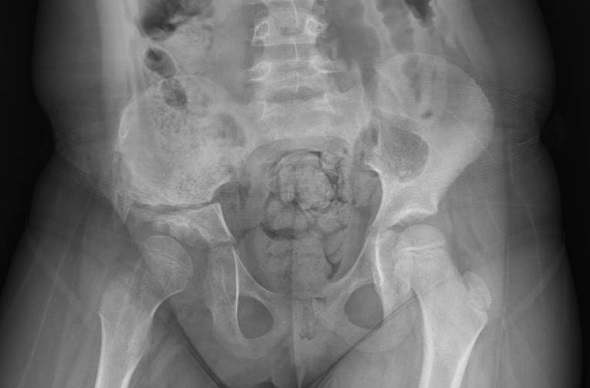

La cirugía Uniportal avanzada, (Video-Assisted Thoracoscopic Surgery, VATS en sus siglas en inglés) es pionera en el mundo, ya que permite extirpar a través de una única incisión los tumores más enrevesados. Posee innumerables ventajas para el paciente: menor dolor postoperatorio y a largo plazo, mayor recuperación funcional, menor índice de complicaciones, mejor resultado estético y la posibilidad de un alta precoz en la mayor parte de los casos. Esto permite al paciente y su familia estar en casa a las 48 horas después de haber sido realizada una cirugía mayor. Existen muchos estudios que demuestran las ventajas de este abordaje comparado con las resecciones por toracotomía.